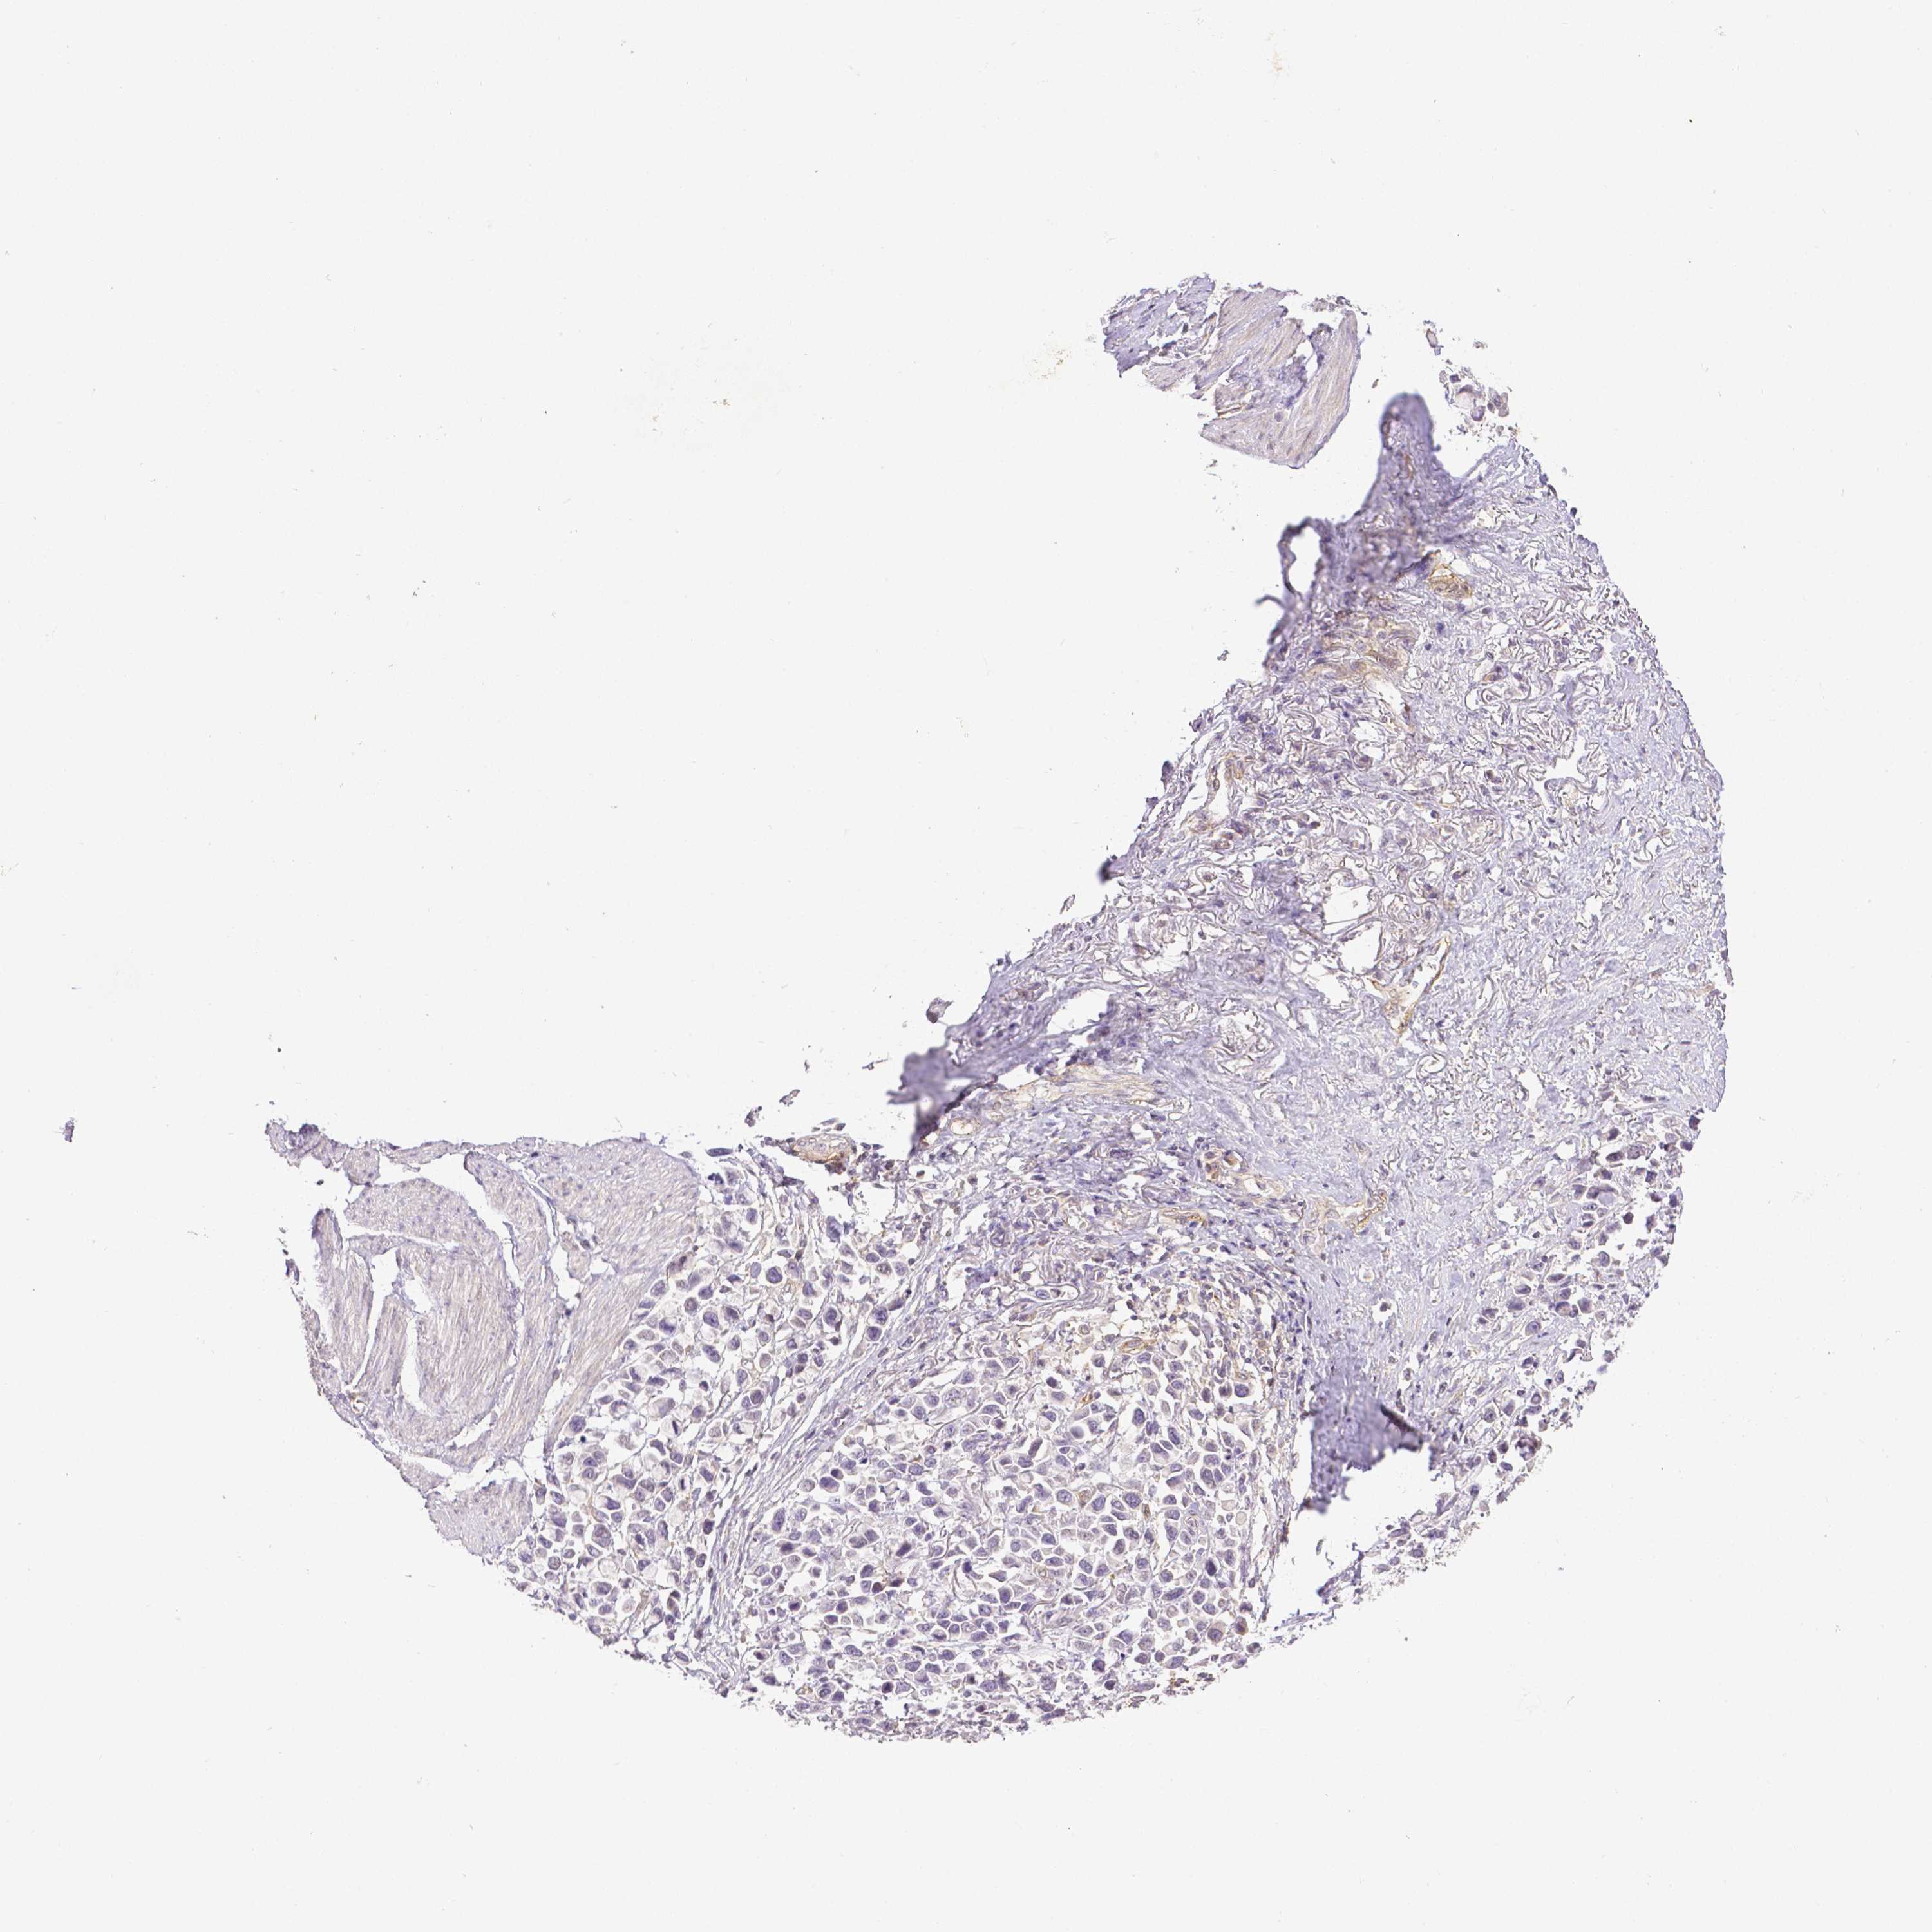

STOMACH CANCER - Protein expressioni

A mouse-over function shows sample information and annotation data. Click on an image to view it in a full screen mode. Samples can be filtered based on level of antibody staining by selecting one or several of the following categories: high, medium, low and not detected. The assay and annotation is described here.

Note that samples used for immunohistochemistry by the Human Protein Atlas do not correspond to samples in the TCGA dataset.

Antibody stainingi

Antibody staining in the annotated cell types in the current human tissue is reported as not detected, low, medium, or high, based on conventional immunohistochemistry profiling in selected tissues. This score is based on the combination of the staining intensity and fraction of stained cells.

Each image is clickable and will lead to virtual microscopy that enables deeper exploration of all samples and also displays staining intensity scores, fraction scores and subcellular localization as well as patient and tissue information for each sample.

Antibody HPA003733

Antibody CAB068243

Antibody CAB068244

Staining

High

Medium

Low

Not detected

Intensity

Strong

Moderate

Weak

Negative

Quantity

>75%

75%-25%

<25%

None

Location

Nuclear

Cytoplasmic/membranous

Cytoplasmic/membranous,nuclear

Adenocarcinoma, NOS